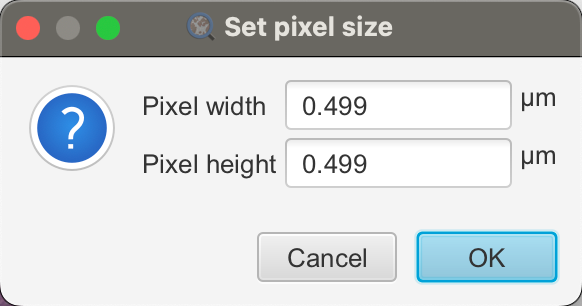

1-4:设置像素大小

如果存储在图像文件中,QuPath 应自动获取像素大小并将其显示在**“图像”**选项卡(“像素宽度”和“像素高度”)下。

如果没有,您可以通过双击任一行并输入正确的值来手动设置像素大小。